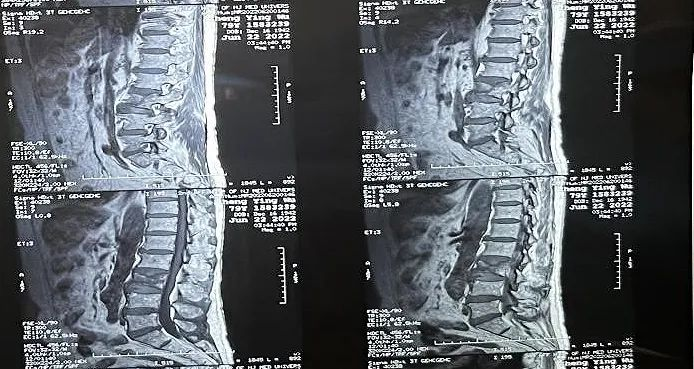

患者情況:腰椎L3壓縮性骨折

南京醫(yī)科大學(xué)第二附屬醫(yī)院骨科副主任醫(yī)師王伯堯帶領(lǐng)團(tuán)隊(duì)成功完成經(jīng)皮椎體球囊擴(kuò)張成形術(shù)(PKP)。該患者為腰椎陳舊性壓縮性骨折,腰部疼痛難忍,活動(dòng)受限,生活受到影響。王醫(yī)生借助普愛醫(yī)療大平板C臂機(jī)高清的圖像及靈活的擺位,快速定位椎弓根位置,確定進(jìn)針點(diǎn),使得手術(shù)得以更加高效和準(zhǔn)確地完成。

患者術(shù)前影像